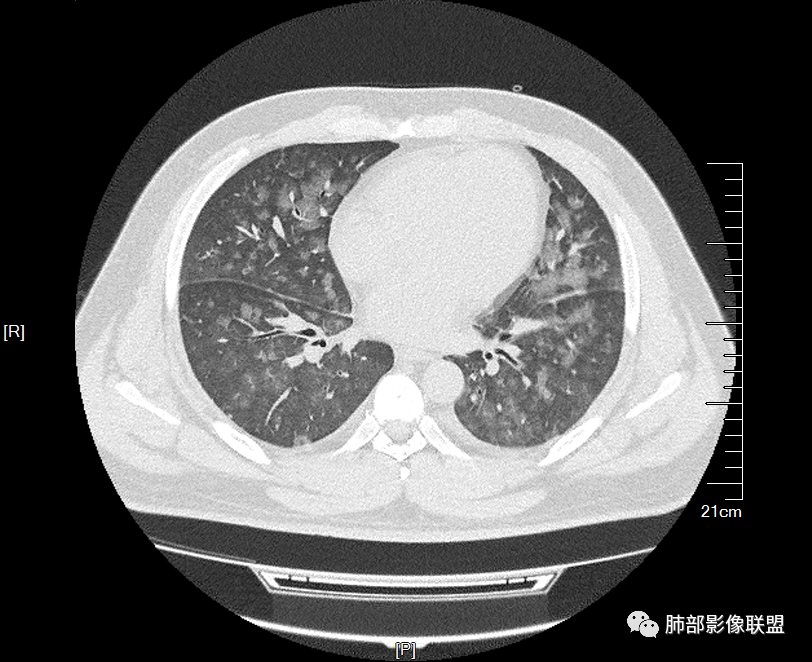

双肺多发弥漫性磨玻璃结节影,大小不一,形态不规则,部分融合,支气管未见明显扩张,部分血管束略增粗,叶裂胸膜增厚,临床有痛风,左足痛6天,考虑:1:痛风结节(一般实性结节,很少磨玻璃结节影)2:血管炎?3:病毒性肺炎(水痘-疱疹肺炎?)

双肺多发腺泡结节及磨玻璃,小叶间隔增厚(大网格状),腺泡结节内及磨玻璃内可见细网格影(小叶内间隔增厚),影像表现符合肺泡出血改变,血肌酐升高,考虑肺肾综合征。鉴别肺水肿。

两肺弥漫向心分布的腺泡结节,部分融合,两肺小叶间隔增厚,血肌肝高,考虑肺泡性肺水肿

年轻男性,痛风史,高血压史,肌酐高,左足痛6天入院。胸CT:双肺多发弥漫性磨玻璃结节影,大小不一,部分融合,上中下肺都有,中内带多,胸膜下少。部分血管束略增粗,小叶内间隔、小叶间隔增厚,下肺明显,左室大。叶裂胸膜增厚。临床有痛风,左足痛6天,考虑:心衰、间质性肺水肿?弥漫性肺泡出血?鉴别:MPA,肺肾综合征,痛风结节等。

年轻男性,痛风,肌酐高,提示肾功能有损,两肺多发磨玻璃腺泡结节,小叶间隔增厚,双侧少许胸水,血管增粗,考虑肾性肺水肿,DAD,鉴别肺肾综合征,需要更多临床资料

小叶间隔增厚,无明显重力趋势

这里有一点重力趋势

中轴间质增厚,小叶间隔增厚,小叶内间质增厚,部分重力作用,双侧对称,胸水,按理淋巴道回流受阻有

1.间质性肺水肿 :小叶间隔增厚,尚光滑,支气管血管束增粗,胸膜或叶间裂增厚,肺内有磨玻璃密度影,有重力分布趋势。

(1)中央型分布:以肺门为中心,两肺中内带对称分布的大片状实变,称为“蝶翼征”。常见于心源性及肾源性肺水肿患者。也可表现为磨玻璃密度病灶,弥漫性分布或以小叶中心性分布。